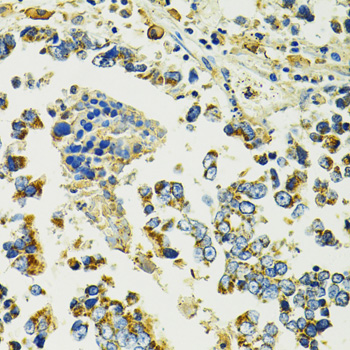

Immunohistochemistry of paraffin-embedded rat spleen using SLC25A11 at dilution of 1:100 (40x lens).

Immunohistochemistry of paraffin-embedded human colon carcinoma using SLC25A11 at dilution of 1:100 (40x lens).

Immunohistochemistry of paraffin-embedded human gastric cancer using SLC25A11 at dilution of 1:100 (40x lens).